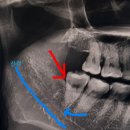

소독 하러 방문하고 일주일뒤엔 실밥 뽑으러 방문..! 사진찍으니 오른쪽 사랑니 없음 ㅎㅎㅎ 왼쪽이 남음 ^_ㅠ... 왼쪽도 왜 매복인게냐,,, 왼쪽은 다음 기회에!! ㅎㅎ ​ 치과 공포증이 있다면 사랑니 발치는 죽파치과 추천합니동 >< ​ #포항죽파치과#죽파치과#사랑니발치#포항사랑니발치#포항사랑니치과#포항사랑님발치후기

피하고만 있던 사랑니 발치 아랫니는 누워서 자라고있는 매복사랑니 애증의 사랑니 몇번이고 맘먹고 포기하다가 드디어 발치에 성공하고 온 후기 정보는 요기⤵️ 💓 죽파치과 💓 ​ 주소: 포항시 북구 중흥로 277 4층 영업시간: 월-금 11:00-20:00 접수마감: 19:15 휴게시간: 16:00-17:00 전화번호: 0507-1405-9899 주차장...

포항 죽파치과를 방문했습니다. 왼쪽 위아래 사랑니(사진상 오른쪽 위아래) 🏥 첫 방문 – CT 촬영 & 발치 가능 여부 확인 첫째 날은 퇴근하고 바로 병원에 들렀어요. CT를 찍고 원장님께 설명을 들었는데, 👉 매복이긴 하지만 발치 가능 👉 대학병원까지는 안 가도 된다고 하셔서 완전 살았어요…😭 그래서 크리스마스 연휴...